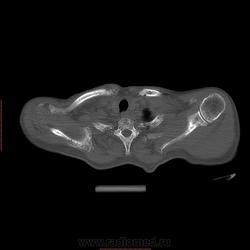

Пациент 1946 г.р., состоит на Д учете в онкодиспансере по поводу с-ч кожи (базалиома), прошел курс лучевой терапии, в 2009г на Ргенографии выявили образование 7 ребра, направили на Кт, на КТ (2009г) был выставлен д-з ГКО, пункционная биопсия не произведена. А сейчас вот такая картина, с множественными литическими очагами в костях грудного склета + образование 7 ребра, с отрицательной динамикой.

повторно взяли пациента, сняли кости таза, такая же картина- множественные очаги литической деструкции. Заключение: больше данных за миеломную болезнь.